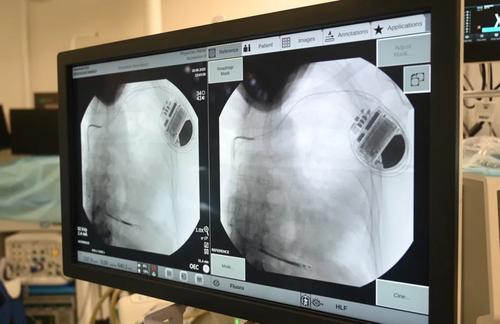

Год назад в рамках развития высокотехнологичной медицинской помощи (ВМП) в московских клиниках бесплатно начали проводить имплантации подкожного кардиовертера-дефибриллятора. Прибор следит за возникновением аномальной сердечной частоты, может восстановить ритм или автоматически выполнить дефибрилляцию при необходимости, таким образом предотвратить внезапную сердечную смерть у пациентов с опасными формами аритмии или тахикардии. С момента внедрения нового метода врачи провели уже 18 таких операций, сообщила заместитель Мэра Москвы по вопросам социального развития Анастасия Ракова.

Подкожный кардиовертер-дефибриллятор устанавливается под широчайшую мышцу спины в подмышечной области, а электрод проводится подкожно на переднюю грудную стенку и устанавливается в проекции сердца. Прибор контролирует активность сердца и, когда оно останавливается, начинает биться неправильно, слишком медленно или слишком быстро, благодаря специальным алгоритмам аппарат посылает электрические импульсы, позволяющие восстановить нормальный сердечный ритм.